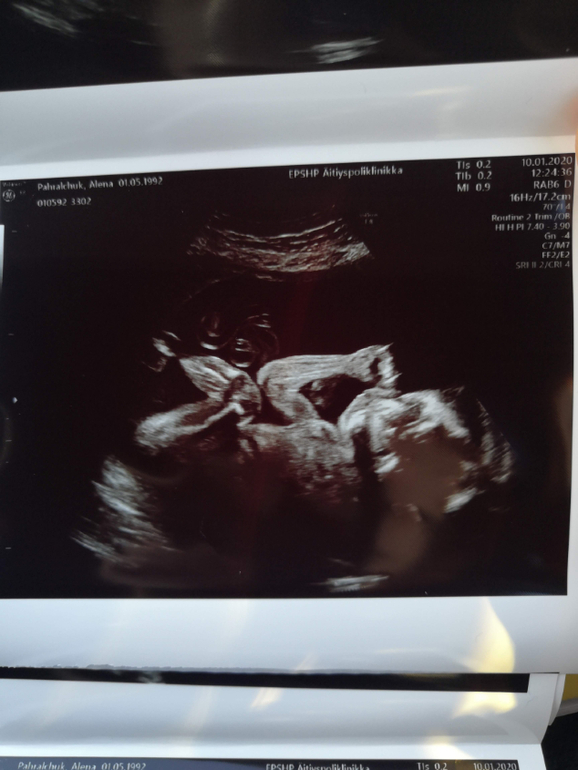

2й скрининг, наконец-то узнали кого ждём!

Сегодня 21 неделя ровно (по сроку с первого скрининга). Так ждала этого 2го скрининга, так ждала... хоть и всё равно кто будет - мальчик или девочка, любопытство распирало узнать 😅

100% сынуля <3

По узи срок на неделю больше, 22 недели ровно. На первом скрининге на 5 дней меньше был. Всё хорошо, растём быстро, хорошо развиваемся. 450гр уже мой маленький мужчина 😁 Весь в папу, папа у нас большой. Плацента высоко, всё ок.

Малыш много вертелся, пальцы сосал, так и не дал себя хорошо в 3Д сфоткать. Ну ничего, в мае увидим всё равно.